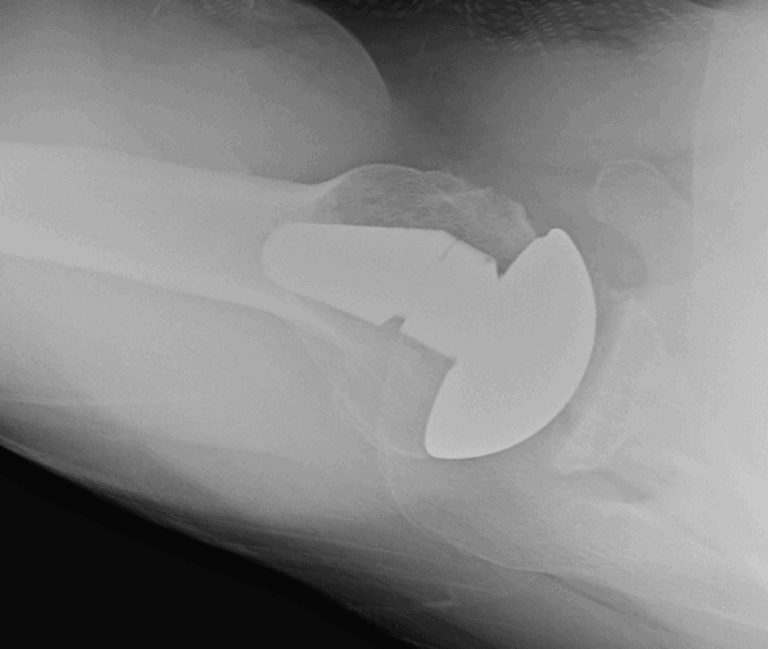

Arthrex, Apex